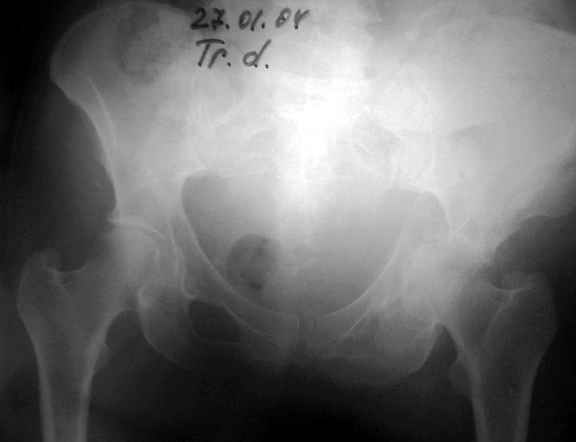

Уважаемые коллеги,Мужчина 36 лет от роду попал в ДТП 24.08.04 Рентгенограммы в приложении.

Диагноз- перелом с вовлечением таза, разрыв правого сакро-илиак сочленения vertical shear injury, перелом крыла подвздошной кости?, перелом ацетабулум Т type или Both column?, перелом шейки бедра, перелом проксимального отдела бедра.

перелом крыла правой подвздошной кости, перелом обеих колонн вертлужной впадины, двусторонний перелом лонных костей (С2.2) повреждение передних связок правого крестцово-подвздошного сочленения,

ипсилатеральный перелом шейки и диафиза бедра.